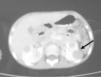

TC cervical y toraco-abdominal (fig. 1): múltiples adenopatías en la región cervical izquierda, con zonas de calcificación central y a nivel retroperitoneal con afectación renal bilateral. Radiografía de tórax: normal. Biopsia ganglionar cervical: enfermedad de Castleman; forma mixta con predominio hialino-vascular.